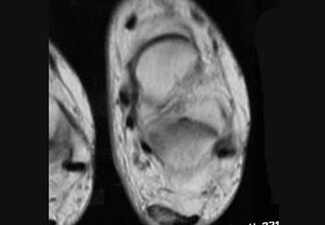

Resonancia magnética nuclear donde se observa el engrosamiento del tendón de aquiles.